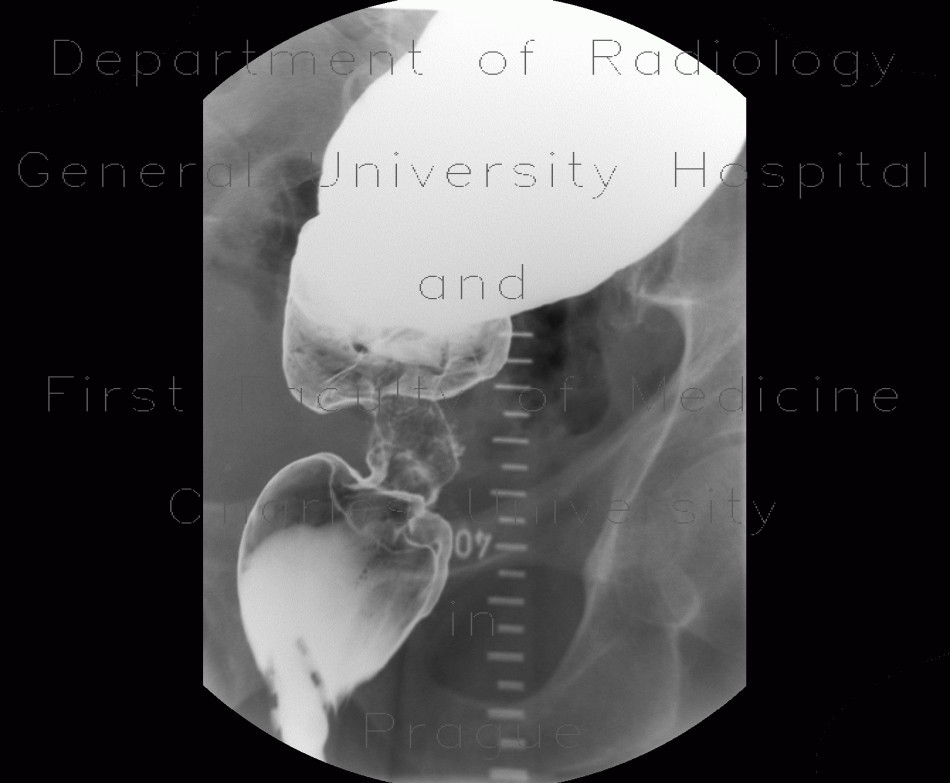

Descending colon stenosis As A Complication Of ... - Termedia

Przegląd Gastroenterologiczny 2009; 4 (1) Descending colon stenosis as a complication of acute pancreatitis Zwê¿enie zstêpnicy jako powik³anie ostrego zapalenia trzustki ... Retrieve Here